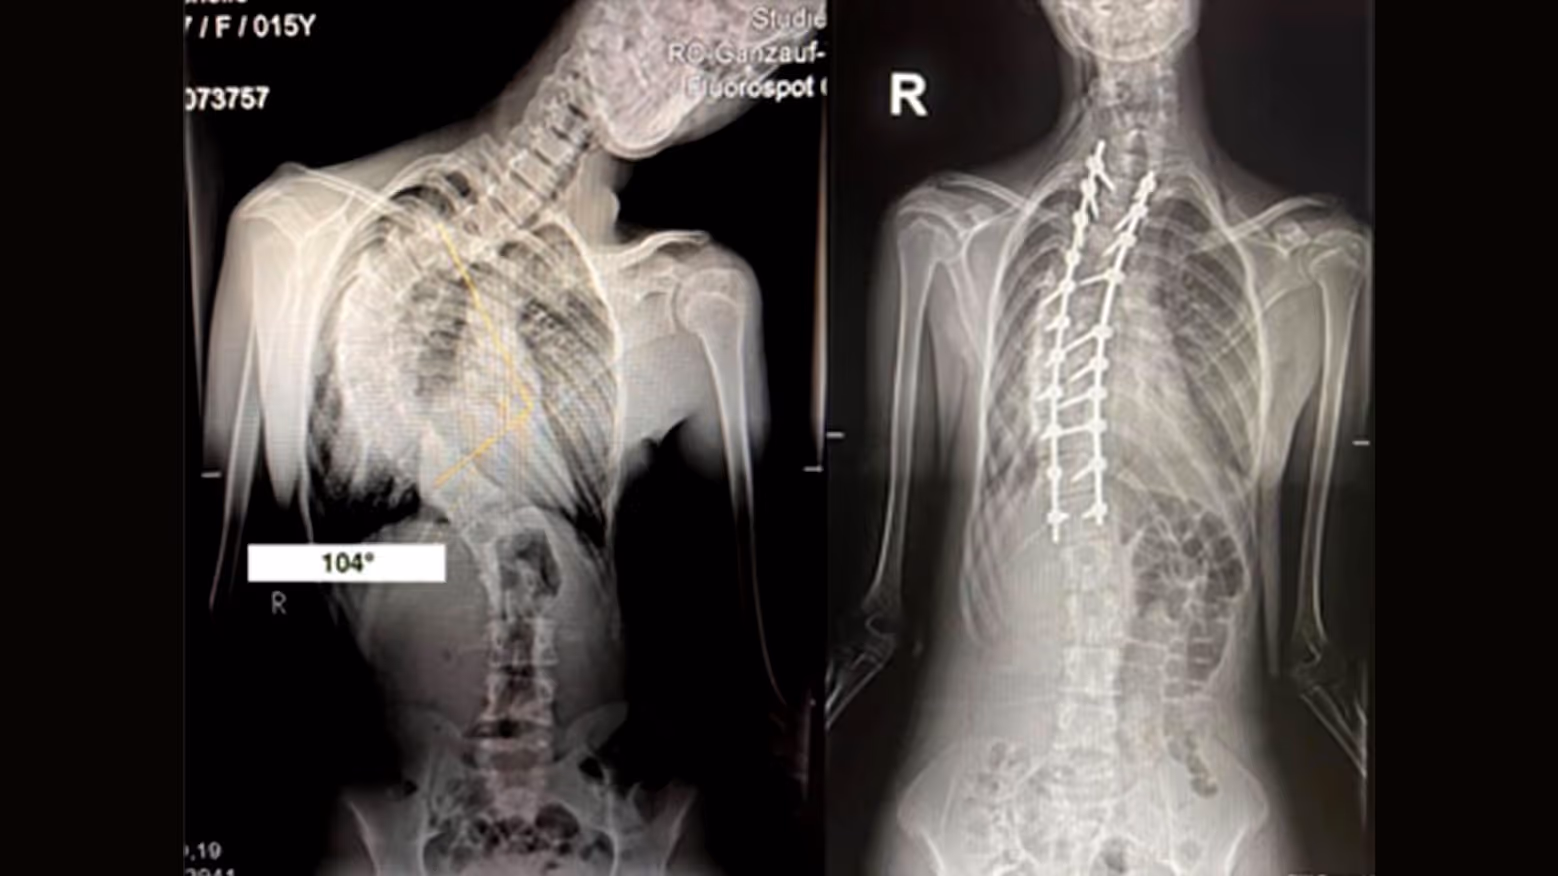

Severe scoliosis (curves greater than 40-50 degrees) may require surgery. The most common procedure is spinal fusion, where metal rods and screws correct and stabilize the spine.

For rigid scoliosis curves greater than 45°, spinalfusion surgery is typically recommended. This procedure involvespermanently connecting two or more vertebrae to prevent further progression ofthe curve and to correct spinal alignment. The surgeon places rods, screws, orother hardware to hold the spine in the corrected position while bone graftshelp fuse the vertebrae together over time. Spinal fusion is effective forstabilizing the spine and reducing severe curves

Examples:

Your child can live his/her life normally after both methods. The modern instrumentation allows full ambulation directly on the first postoperative surgical day without the need for any braces or corsets. The hospital stay is around 5 days. He can re-visit his school 3 to 4 weeks after the surgery.Contact sports could be continued 6 months after the operation. The operation does not cause any restriction in job selection afterwards when the children are grown up and definitely do not have any disadvantage regarding fertility and pregnancy.